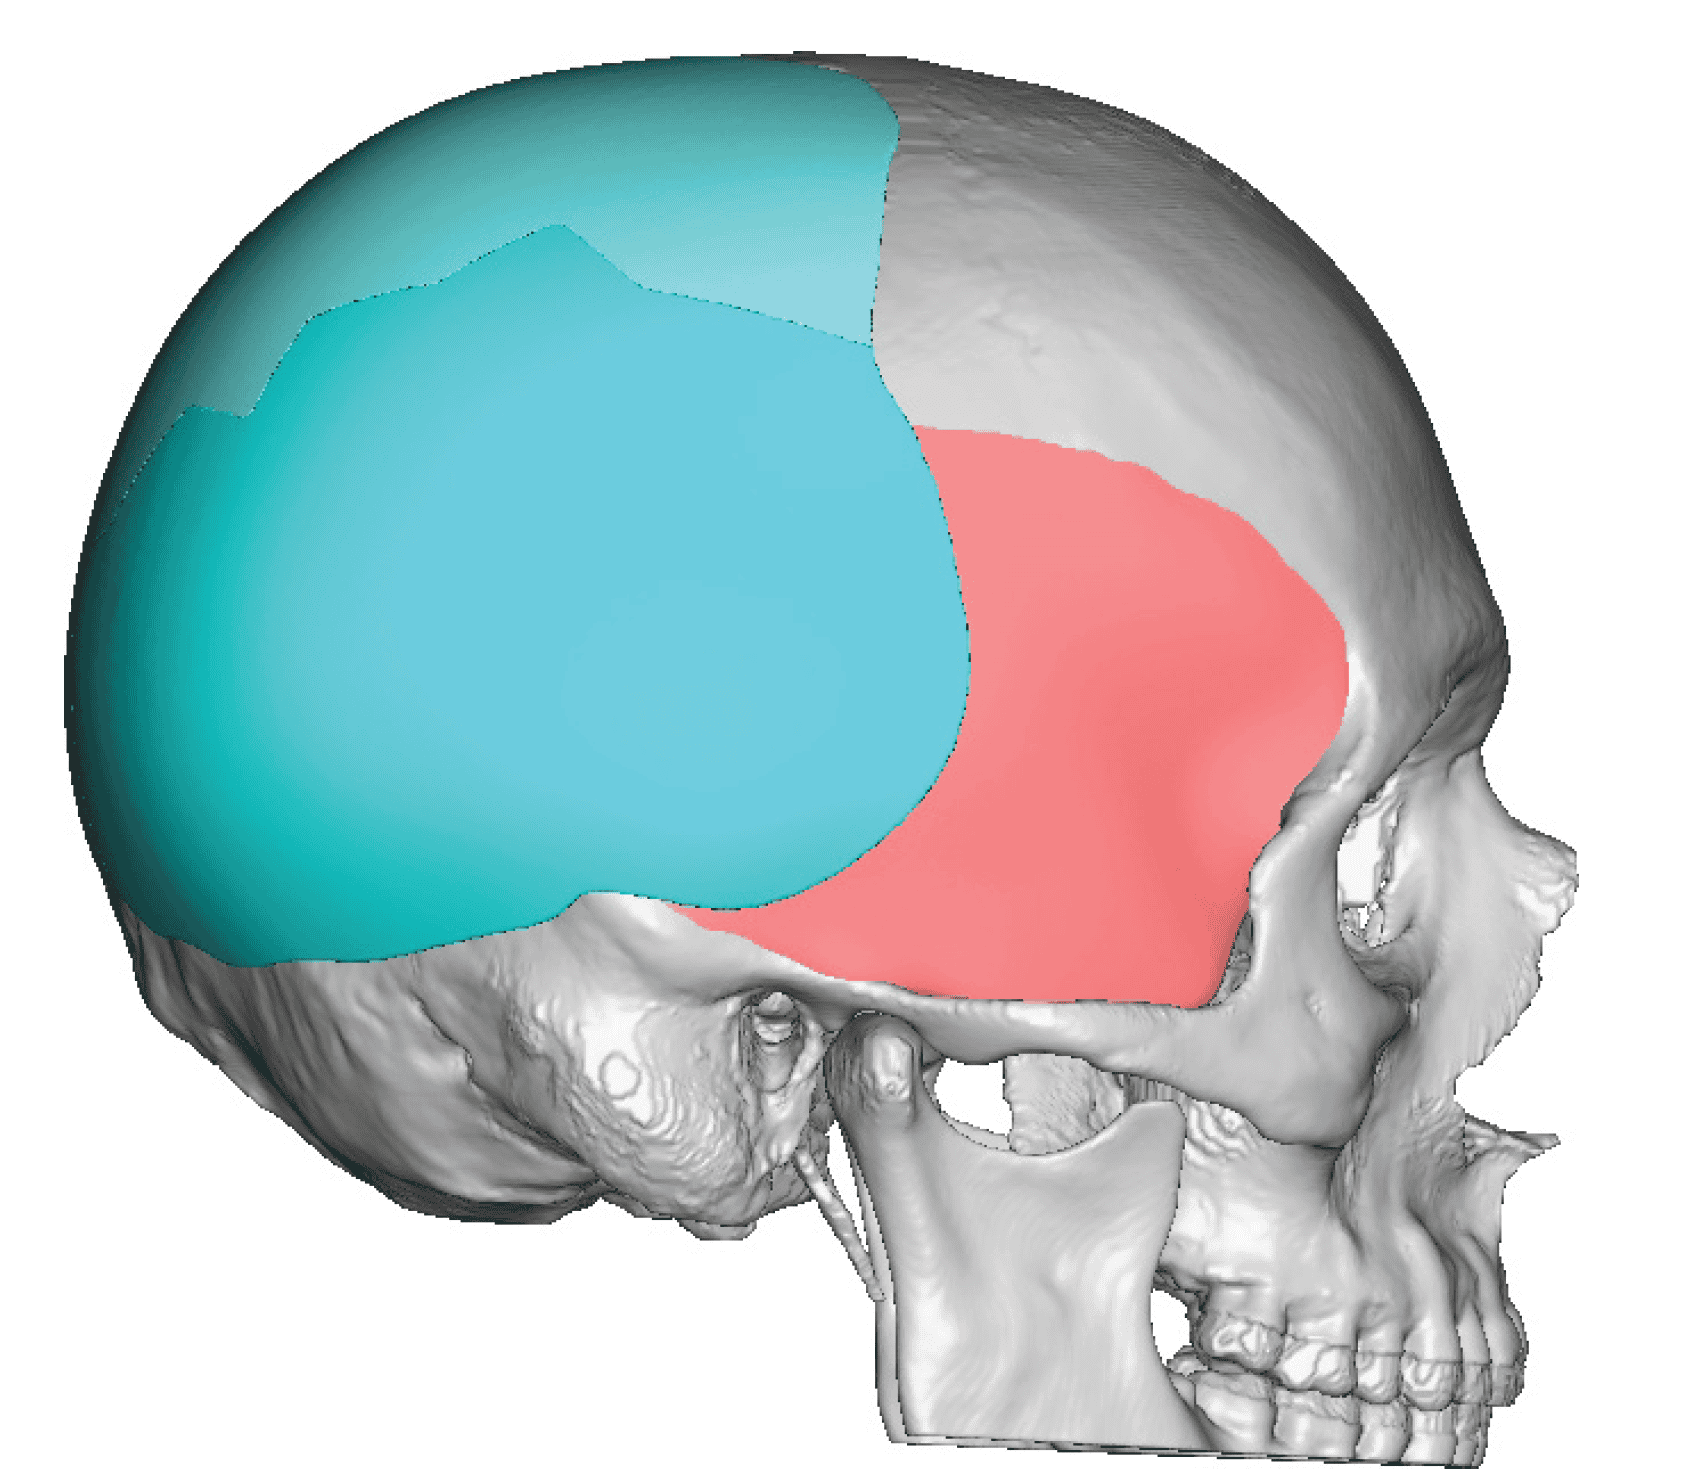

Desire for change of head shape from front view form an inverted V shape to a rounder and wider head shape.

Placement of custom extended forehead-temporal implants through incisions in the crease behind the ear. (he had a prior back of head skull implant which is green in the implant designs and which the head widening implants partially covered it)

Desire for change of head shape from front view form an inverted V shape to a rounder and wider head shape.

Placement of custom extended forehead-temporal implants through incisions in the crease behind the ear. (he had a prior back of head skull implant which is green in the implant designs and which the head widening implants partially covered it)